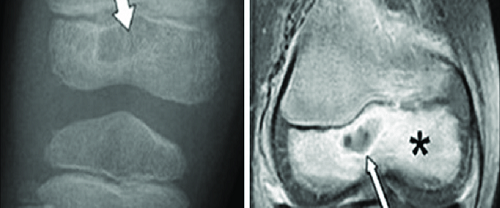

Osteokondral Greft Transfer Sistemi Osteokondral Greft Nedir? Osteokondral Greft Transfer Sistemi | Osteokondral greft, genellikle eklem yüzeylerindeki hasarı düzeltmek için kullanılan bir cerrahi prosedürdür. Greft, hem kemik hem de kıkırdak içeren bir dokudur ve genellikle alıcı bölgeye nakledilir. Bu yöntem, kıkırdak hasarı, kıkırdak delikleri veya kıkırdak kaybı gibi durumları tedavi etmek için kullanılır. Greft, hastanın…